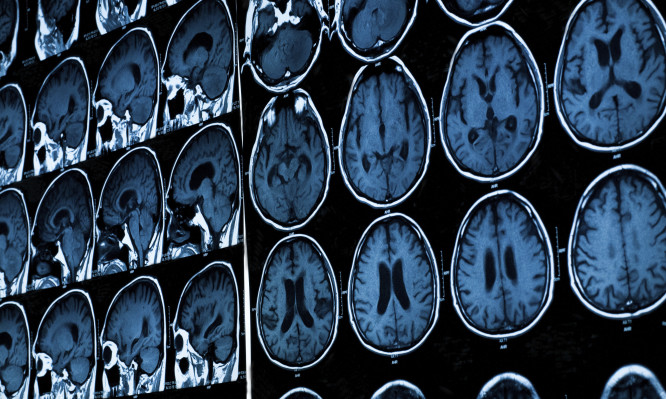

Ο ανθρώπινος εγκέφαλος απεικονίζεται πια μέχρι τελευταίου κυττάρου

Ένα από τα τέσσερα συστήματα MRI που θα χρησιμοποιηθούν επιτόπου, το Magnetom Skyra Connectom 3T1, είναι αυτή τη στιγμή το μοναδικό στο είδος του στην Ευρώπη. Η προηγμένη τεχνολογία του θα επιτρέψει στους επιστήμονες να μελετήσουν τις δομές στο φάσμα micron (δηλαδή στο χιλιοστό του χιλιοστού). Διαθέτει βαθμιδωτά πηνία 300 mT/m που είναι 6 φορές ισχυρότερα από τα αντίστοιχα των συμβατικών συστημάτων MR. Αυτό θα επιτρέψει στους ερευνητές να εξετάσουν τη μικροδομή των ιστών με πολύ μεγαλύτερη λεπτομέρεια και σε περαιτέρω βάθος.